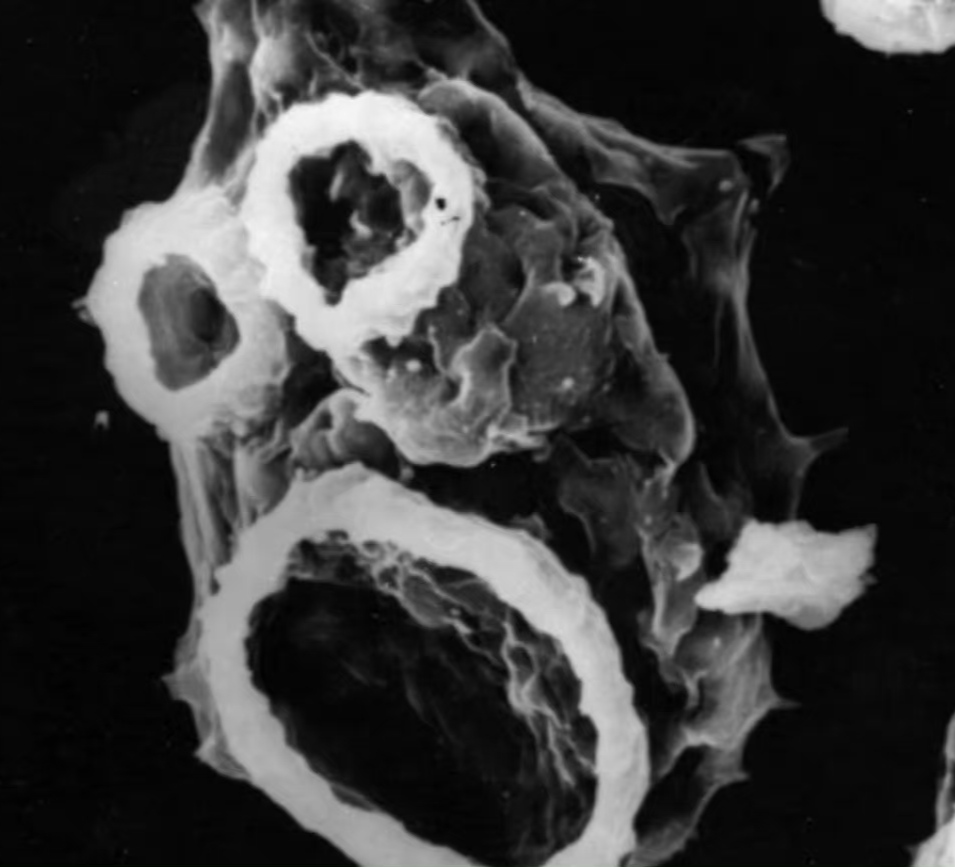

自来水中食脑的福氏耐格里阿米巴

恐怖食脑虫——阿米巴变形虫

致命的"食脑" 阿米巴原虫